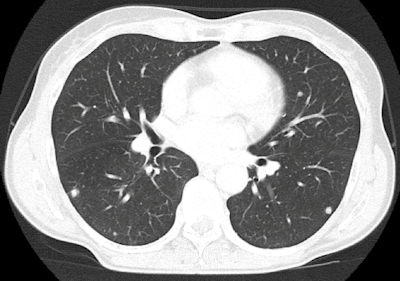

"The introduction of larger, more powerful devices (such as the iPad 2) is likely to further expand this kind of application, with some surgeons already using it in the operating room to assist interventions," Faggioni said. For instance, the following images of CT pulmonary embolism and knee MRI, as well as the chest CT image of lung nodules above were exported from an iPad 2. "Diagnosis could have been made on it without the need of a workstation," he said.